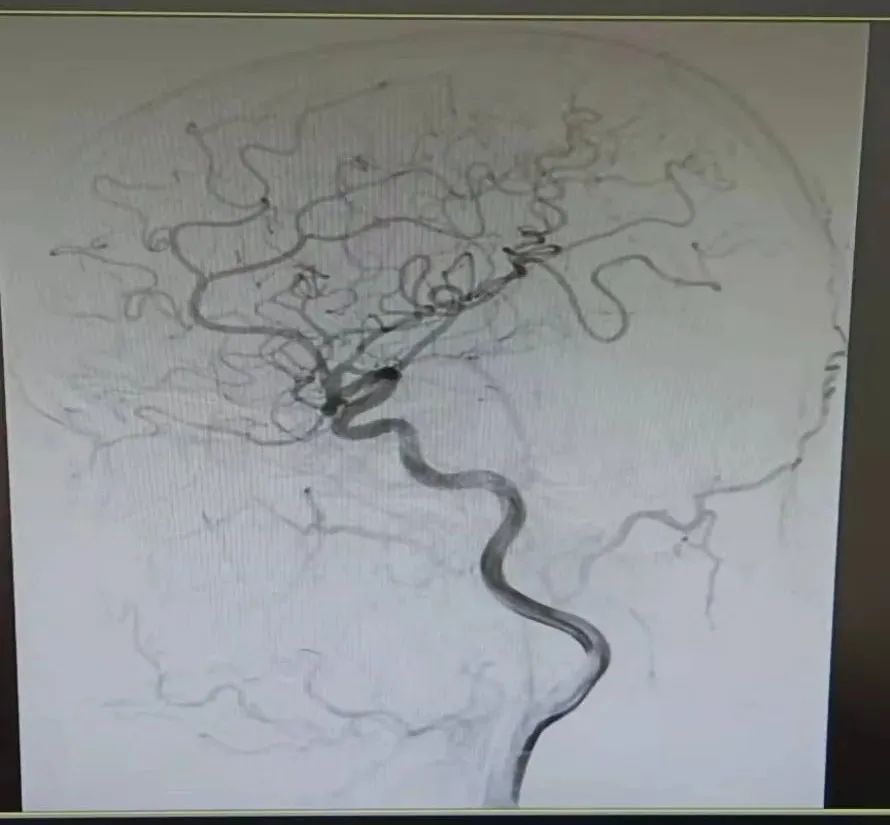

全脑血管造影是广泛应用于临床的一种崭新的X线检查新技术,是应用含碘造影剂注入颈总动脉、颈内动脉、椎动脉,在不同时期显示脑内动脉、回流静脉和静脉窦的形态、部位、分布和行径的一种显影技术。脑血管造影分为常规脑血管造影和数字减影脑血管造影(DSA)。DSA具有简便快捷、血管影像清晰、可选择性拍片、并发症少等优点,病程短,愈合良好。因而常规脑血管造影已被数字减影脑血管造影所取代。能清楚的显示颈内动脉、椎基底动脉、颅内大血管及大脑半球的血管图像,不但可以提供脑部病变的确切部位,而且对病变的范围及严重程度也可以很清楚的了解,还可以测定动脉的血流量,所以目前已被广泛应用于脑血管病检查,目前通常采用股动脉或桡动脉插管法做全脑血管造影。

在DSA开机启用的背景下,我院介入导管室的成立填补了心内科、神经內科、神经外科等多学科介入治疗的空白,提升了我院综合救治能力,真正打造救命的“高速公路”。介入导管室成立至今,共开展冠脉动脉造影术、冠状动脉内支架置入术168台,经股动脉插管全脑动脉造影术8台,手术总费用达80万余。科学有效的护理干预是保障手术顺利进行的重要策略,追求严格的护理操作和耐心细致的心理疏导,为广大患者提供方便、快捷、高效的优质护理服务。